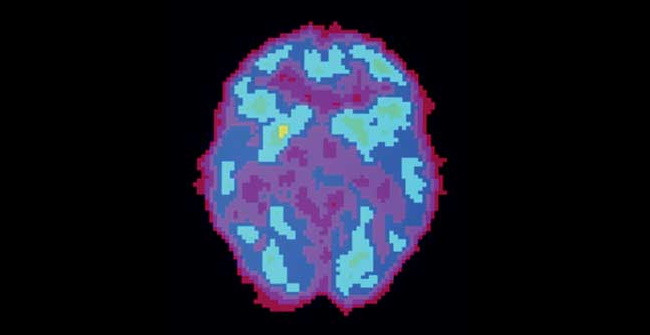

Активность мозга сильно различается не только во время бодрствования и сна — есть множество промежуточных состояний, которые можно различить во время позитронно-эмиссионной томографии.